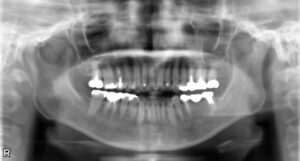

下顎大臼歯2本欠損症例

BEFORE AFTER 44歳女性/下2本欠損/インプラント埋込手術 【治療内容】 5年ほど前に他院で治療した左下のブ…